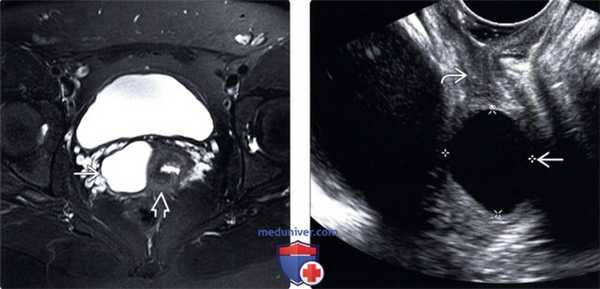

(Левый) На сагиттальном трансабдоминальном УЗ срезе таза в верхнем отделе влагалища визуализируется овальная киста. Нижний отдел влагалища и мочевой пузырь в норме.

(Правый) На продольном трансвагинальном УЗ срезе (эта же пациентка) с минимальным давлением киста кажется более круглой. Матка и мочевой пузырь в норме.

(Левый) На продольном трансвагинальном УЗ срезе с цветовой допплерографией у этой же пациентки отсутствует цветовой ток в кисте гартнерова хода.

(Правый) На парасагиттальном Т2 FS МР срезе визуализируется однокамерная Т2-усиленная киста гартнерова хода в верхнем отделе влагалища. Мочевой пузырь и матка без изменений.